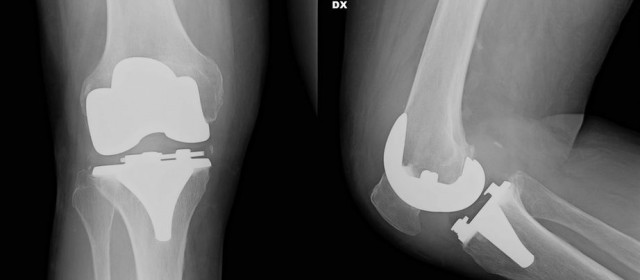

La novità consiste nella personalizzazione della protesi: prima di operare, infatti, viene fatta una TAC (acronimo di tomografia assiale computerizzata) che studia l’osso, permettendo all’ingegnere e al chirurgo di adoperare una serie di scelte esclusive per quel ginocchio e per quel paziente. La protesi, che viene installata in un’ora, è quindi un abito su misura, e consente un recupero totale del ginocchio. Questo protocollo nasce in Svizzera e si è diffuso soprattutto in Francia e Spagna, ma poco in Italia. Attualmente sono solo quattro i centri a cui ci si può rivolgere: a Genova, a Roma, ad Arezzo e a Bologna. Gli interventi di protesi di ginocchio nel 2014 sono stati circa 85mila in Italia e sono sicuramente in aumento.

“La qualità dei risultati – precisa il Mario Manili ortopedico, Socio SIOT – Società di Ortopedia e Traumatologia- Consulente presso il Centro Chirurgico Toscano di Arezzo e la Clinica Villa del Rosario di Roma – dipende dalla precisione dell’applicazione della protesi, perché bisogna togliere la parte malata, riequilibrare l’asse del ginocchio, intervenendo quindi anche sui legamenti, e fissarla all’osso. Tutto questo si fa con un gesto unico, ma richiede un altissimo livello di precisione, altrimenti si rischia un risultato poco efficace. C’è soltanto un 2% dei pazienti che continua a subire un lievissimo dolore, ma di gran lunga inferiore al precedente. Con il tempo però, anche in questi casi, si raggiunge il perfetto equilibrio”.